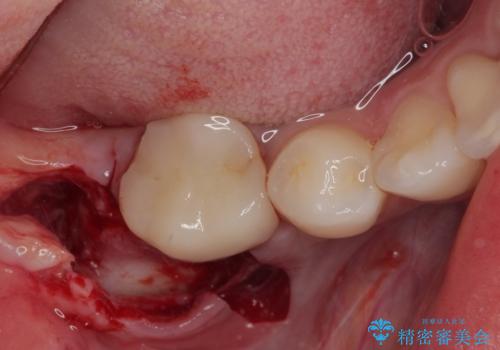

埋伏している右下第二大臼歯は、牽引して咬合に参加させることで計画しましたが、癒着などにより移動困難な場合には、抜歯の上インプラント補綴治療を行うこととしました。

右下の埋伏歯はやはり癒着しており、抜歯の後にインプラントを埋入することとなりました。